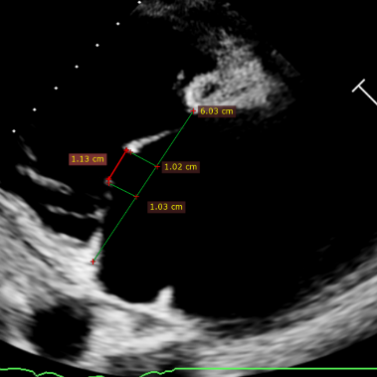

Echocardiographic findings indicated: Type IIIB quadrileaflet tricuspid malformation with extremely severe tricuspid regurgitation (5+, vena contracta: 16.1 mm on average). Regurgitant orifices were located at the anterior-septal, central, and posterior-septal regions, with a 11 mm central gap, leaflet tethering (tethering height: 10 mm), and tricuspid annular dilatation (mean annular diameter: 53 mm). The inferior vena cava diameter was approximately 25 mm, and RV FAC was 40%.

Based on comprehensive evaluation of preoperative CT and echocardiography, the patient presents with severe tricuspid annular dilatation and leaflet tethering. Tricuspid regurgitation originates mainly from the mid-posteroseptal and anteroseptal regions. The distance from the free edge to the posterior annulus was 25 mm, with an RCA‑TA distance <3 mm (closest: 1.4 mm). The procedure is technically challenging. It is planned to deploy a 14T K-Clip® at the posterior annulus and a 16T K-Clip® at the anteroposterior annulus to reduce the annular circumference and increase leaflet coaptation, thereby reducing tricuspid regurgitation.

Preoperative annulus area: 20.6 cm²

After implantation of two clips, the annulus area is 11.8 cm²